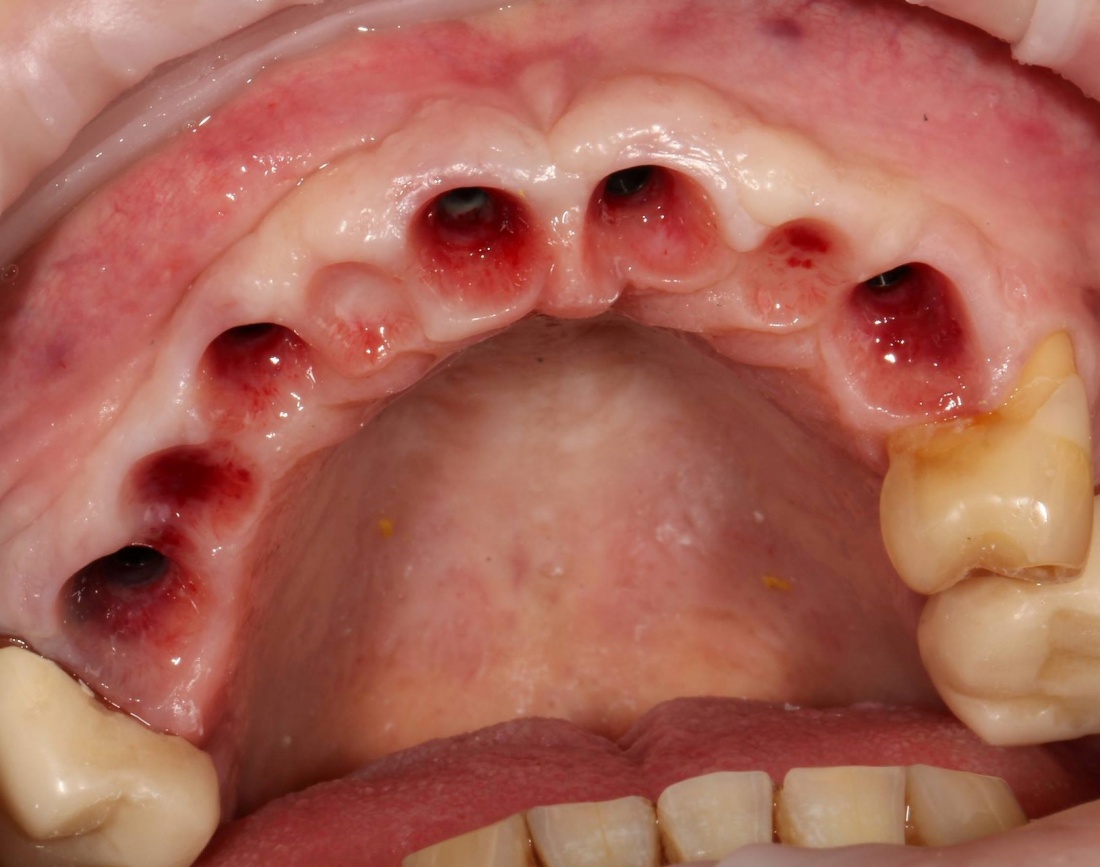

Например, в таком случае:

я бы зассал делать остеотомию предпочёл бы другой метод остеопластики